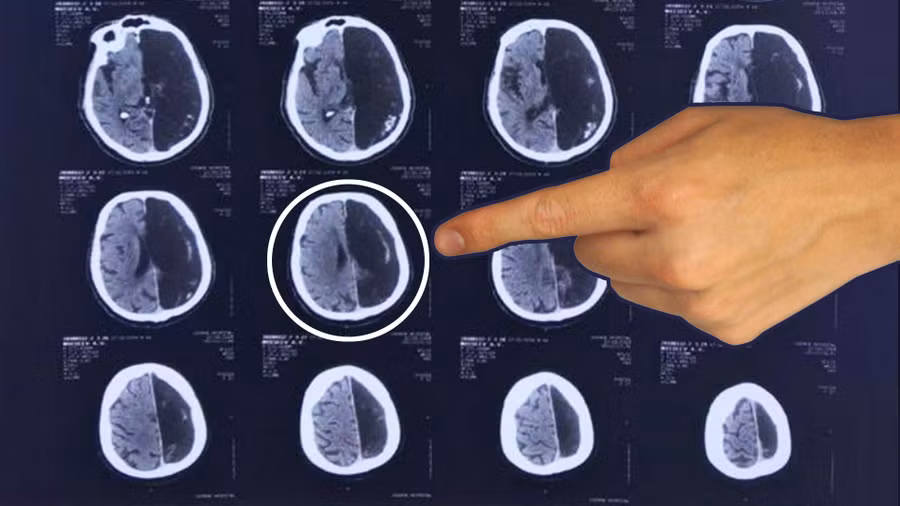

Hình ảnh chụp não của bệnh nhân.

Một trường hợp bệnh nhân ở Moscow đã được bác sĩ phát hiện ra bị mất một nửa bên não theo đúng nghĩa đen. Tuy nhiên, người đàn ông 60 tuổi này vẫn đã và đang sống một cách khỏe mạnh trong hàng chục năm qua mà bản thân không hề biết về tình trạng của mình, tờ RBTH đưa tin.

“Đây là trường hợp độc nhất vô nhị, bởi vì bệnh lý như vậy xảy ra ở giai đoạn sớm nhất trong giai đoạn phát triển não bộ của phôi thai”, nhà thần kinh học Marina Anikina cho hay.

“Đôi khi trường hợp đó có thể dẫn đến tử vong. Tuy nhiên, ví dụ của bệnh nhân này cho chúng ta thấy rằng những trường hợp tương tự luôn có thể tiếp tục cuộc sống một cách bình thường”, Anikina nói.

Nhà thần kinh học giải thích, ở giai đoạn phát triển ban đầu, bộ não con người có thể phân phối lại các chức năng từ bán cầu này sang bán cầu kia vì các chức năng này chưa được neo vào bất kỳ bán cầu não cụ thể nào.

Điều này có nghĩa là mặc dù người đàn ông thiếu một nửa bộ não, ông không có bất kỳ khuyết tật não nào.